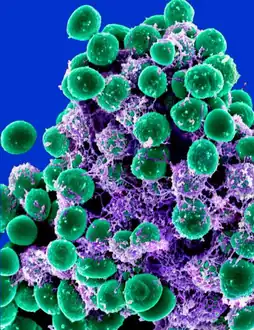

| Scanning electron image of S. epidermidis. | |

Staphylococcus epidermidis is a Gram-positive bacterium, and one of over 40 species belonging to the genus Staphylococcus.[1] It is part of the normal human microbiota, typically the skin microbiota, and less commonly the mucosal microbiota and also found in marine sponges.[2][3] It is a facultative anaerobic bacteria. Although S. epidermidis is not usually pathogenic, patients with compromised immune systems are at risk of developing infection. These infections are generally hospital-acquired.[4] S. epidermidis is a particular concern for people with catheters or other surgical implants because it is known to form biofilms that grow on these devices.[5] Being part of the normal skin microbiota, S. epidermidis is a frequent contaminant of specimens sent to the diagnostic laboratory.[6]

Cellular morphology

Staphylococcus epidermidis is a very hardy microorganism, consisting of nonmotile, Gram-positive cocci, arranged in grape-like clusters. It forms white, raised, cohesive colonies about 1–2 mm in diameter after overnight incubation, and is not hemolytic on blood agar.[5] It is a catalase-positive,[7] coagulase-negative, facultative anaerobe that can grow by aerobic respiration or by fermentation. Some strains may not ferment.[3][8]